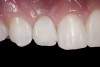

(22.) Right lateral view.

Figure 22

When the patient returned, the fit was evaluated in the mouth. Once verified, the internal surface of the framework was etched with a 9.5% hydrofluoric acid for 90 seconds and then salinized. After etching the enamel surface with phosphoric acid for 30 seconds and applying the primer (Single Bond Plus, 3M ESPE) to both the internal surface of the framework and the enamel, the zirconia bridge was bonded with a dual-cure resin cement (RelyX™ ARC, 3M ESPE). After the procedure, the patient ended up with a long-term, high-strength esthetic restoration advantaged by the bonding potential of fledspathic ceramic (Figure 20 through Figure 24). Six years after placement, the prosthesis had remained in place with no complications.